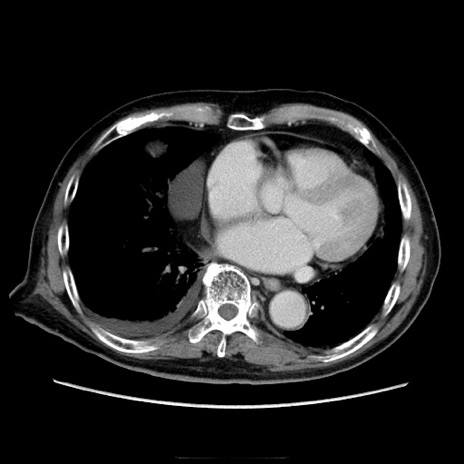

症例21(横断像)

【症例】70歳代男性

【主訴】腹痛

【現病歴】肝硬変・肝細胞癌にてかかりつけの方。約9時間前に食後より腹痛出現。症状が徐々に増悪し、嘔吐出現したため来院。

【既往歴】肝硬変、肝細胞癌(RFA、TACE後)

【身体所見】意識清明、表情苦悶様、BT 36℃、BP 129/78mmHg、P 88bpm、SpO2 97%(RA)、右上腹部から心窩部にかけて圧痛あり、反跳痛なし、筋性防御あり。

【データ】WBC 5800、CRP 0.16